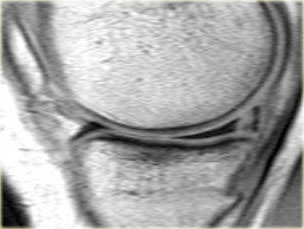

Ghi nhận một đường rách hướng tâm tại vị trí chân sụn chêm phía sau của sụn chêm trong, đường rách xuyên suốt toàn bộ chiều dày sụn chêm với hình ảnh khe dịch lan dọc theo khuyết tổn thương (mũi tên đỏ).

Rách chân sụn chêm thường đi kèm với hiện tượng thoát vị sụn chêm ra ngoài bờ mâm chày.

Thoát vị sụn chêm trên 3 mm thường liên quan đến các tổn thương rách tại vùng chân sụn chêm (6).

Trong trường hợp bên trái, ghi nhận một đường rách hướng tâm hoàn toàn tách rời sừng sau khỏi chân bám của nó (mũi tên đỏ).

Ngoài ra còn có hình ảnh thoát vị sụn chêm mức độ tối thiểu (hình 1/6).